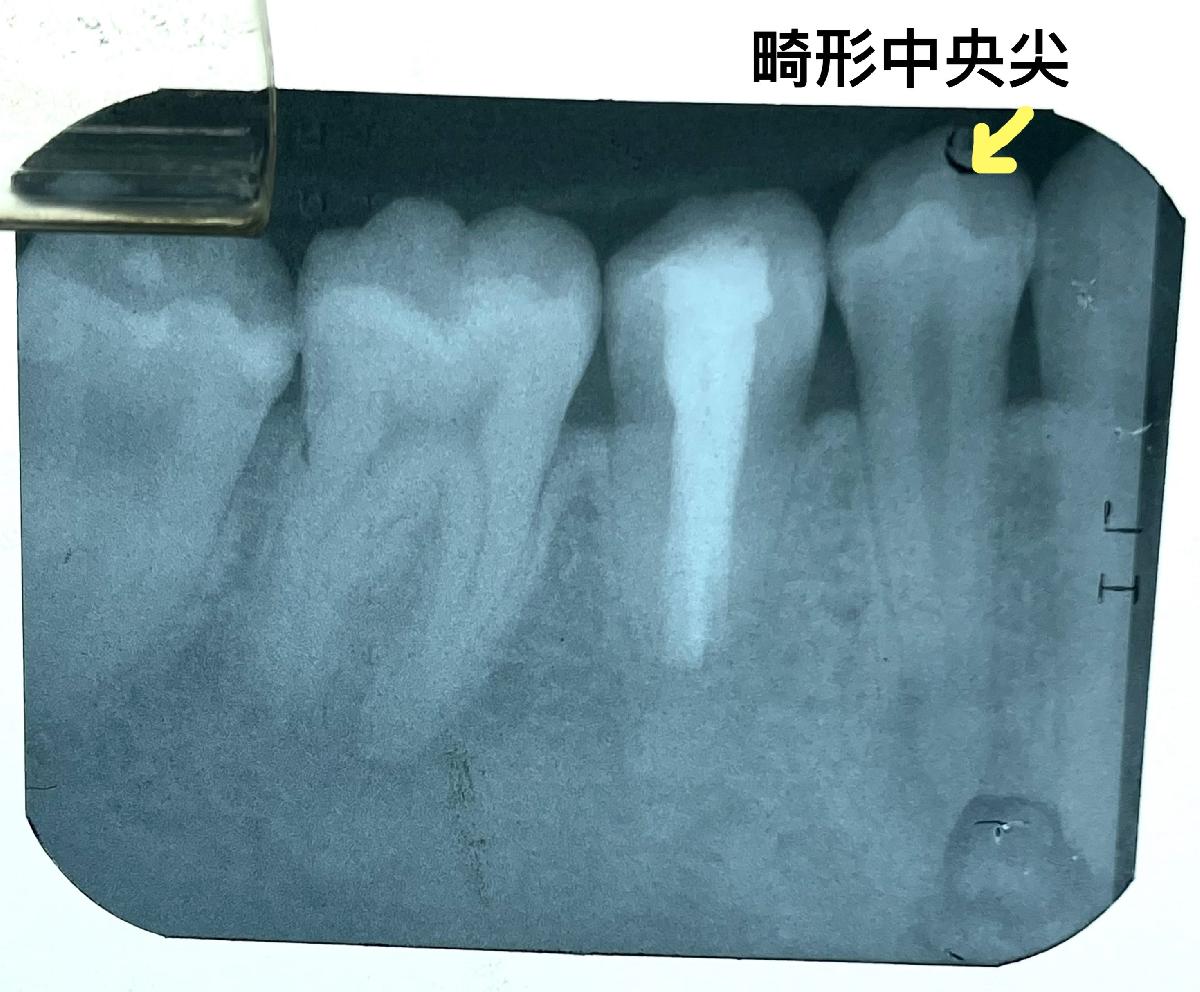

醫師往口內檢查發現,原來下顎小臼齒的咬合面中央多了一個結節;不意外地,在上顎小臼齒上,也有對稱性的發生。此一結節名為畸形中央尖(central cusp deformity),呈圓錐狀突起,高約2-3mm,看起來已受到咬合磨損,根尖X光片則顯示出因牙髓神經壞死而導致的根尖周圍感染。

潘老師接受醫師建議進行根管治療,經過密集回診,從X光片上見到根尖病變處逐漸縮小,牙齒也不再有咬起來怪怪的感覺,讓潘老師終於露出久違笑容。